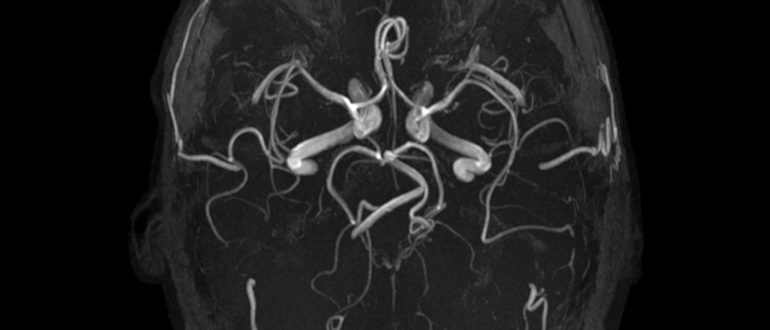

МРТ ГМ. Единичный очаг демиелинизации. Ассиметрия ПА

Очаги демиелинизации на мрт — Все про гипертонию Многие годы безуспешно боретесь с ГИПЕРТОНИЕЙ? Глава Института: «Вы будете поражены, насколько просто можно вылечить гипертонию принимая каждый день… Читать…